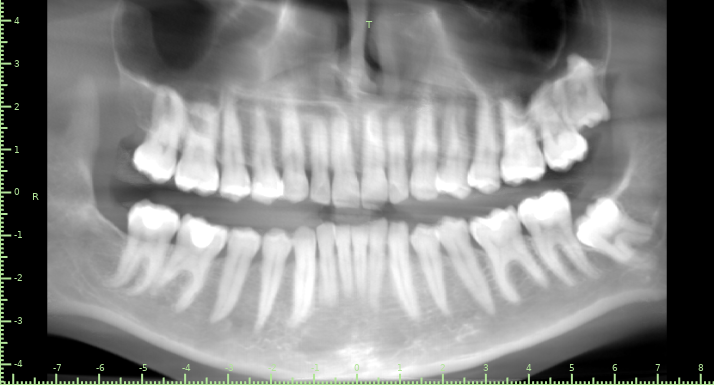

Aristokratka Опубликовано 24 мая, 2025 Поделиться Опубликовано 24 мая, 2025 Записана в зубной только через неделю, была на приеме хотела полечить один жевательный зуб, но врач отправил на КТ. Прошу оценить состояние, чего ожидать (мадам, 34 годика, дважды мама) ? Ссылка на исследование https://disk.picasso-diagnostic.ru/d9c61016-1f1c-4171-ae6d-25aa4e3ec28a/ Заранее благодарю за ответ. Ссылка на комментарий

Женька Опубликовано 25 мая, 2025 Поделиться Опубликовано 25 мая, 2025 Здравствуйте. Да в общем ничего страшного не увидел. Кроме двух кудрявых 8. Нижняя категорически сложная в удалении, на мой взгляд. корни перегибаются через канал нерва нижней челюсти. Я бы рассматривал альтернативы удалению, если вдруг таковое потребуется (коронэктомия, ортоэкструзия на винтах). Верхняя тоже "кудрявая", но такой сложности вроде бы нет. Возможно пломбы заменить, гигиену сделать? Но по снимку этого не оценить никак. Зубы все живые, очагов патологических тоже не нашёл. 2 Ссылка на комментарий

shishok Опубликовано 25 мая, 2025 Поделиться Опубликовано 25 мая, 2025 Есть подозрения на наличие кариозной полости на задней поверхности верхней левой шестёрки. На этом снимке не очень четко видно, можно сделать прицельный снимок. 1 Ссылка на комментарий